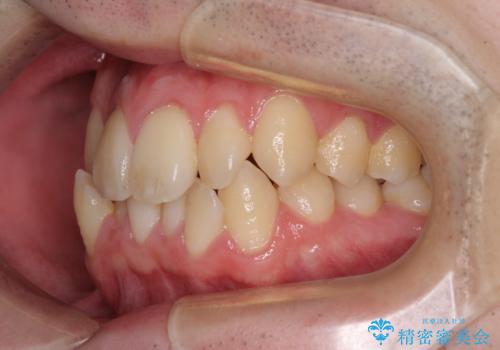

全顎的なクロスバイト 補助装置を用いてワイヤー矯正

- 八重歯や奥歯の噛みにくさを気にして来院された患者様です。

前歯のクロスバイトや八重歯の他に、左右最後臼歯のシザーズバイト(鋏状咬合)が認められました。

シザーズバイト改善のために補助装置を使用しながら、ワイヤー装置にて全体の歯列を整えることとしました。